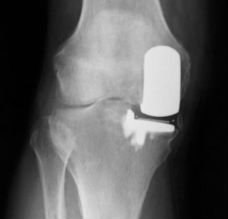

Focal implant

Another option is a focal implant. These are small metal implants designed to replace a focal defect in the joint cartilage without doing anything to the opposing side. Focal implants allow immediate weightbearing, a shorter rehab period and therefore a much quicker return to activity and work. In the image on the right (a model bone) the implant has been placed on the rounded condyle of the femur.

The technique is similar to the resurfacing procedures above, and the implant and its stem are fixed in place with or without cement. Again, there is no major bone block taken and no removal of ligaments or menisci. This may 'buy time' before a knee replacement is needed or may avoid it altogether.